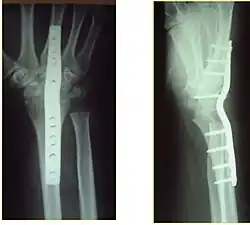

Posttraumatic arthritis of the wrist, degeneration of the articular surface before and after resection

X-rays of a wrist fusion

Surgery

Surgery is generally indicated for displaced or unstable fractures.[18] The techniques of surgical management include open reduction internal fixation (ORIF), external fixation, percutaneous pinning, or some combination of the above. The choice of operative treatment is often determined by the type of fracture, which can be categorized broadly into three groups: partial articular fractures, displaced articular fractures, and metaphyseal unstable extra- or minimal articular fractures.[5]

Significant advances have been made in ORIF treatments. Two newer treatments are fragment-specific fixation and fixed-angle volar plating. These attempt fixation rigid enough to allow almost immediate mobility, in an effort to minimize stiffness and improve ultimate function; no improved final outcome from early mobilization (prior to 6 weeks after surgical fixation) has been shown. Although restoration of radiocarpal alignment is thought to be of obvious importance, the exact amount of angulation, shortening, intra-articular gap/step which impact final function are not exactly known. The alignment of the DRUJ is also important, as this can be a source of a pain and loss of rotation after final healing and maximum recovery.